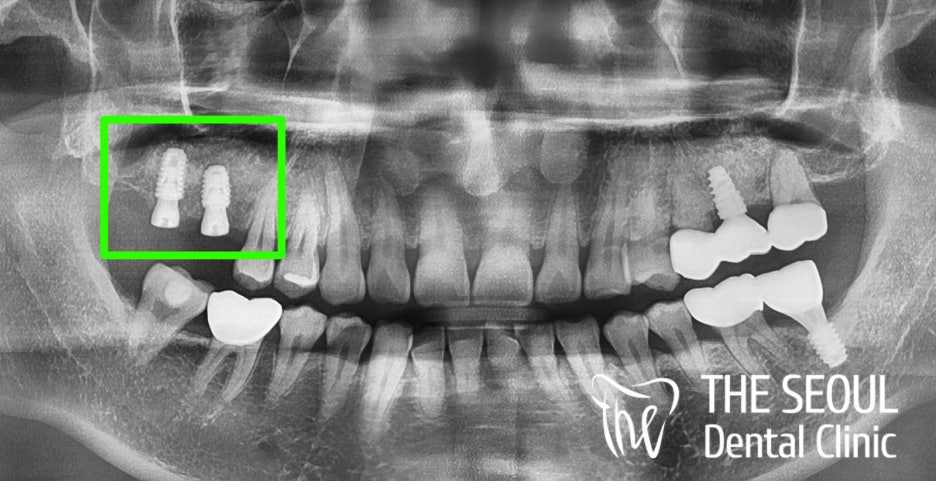

『가이드 임플란트 과정』

병소가 남아있는 어금니를 깨끗하게 발치했습니다.

이후 컴퓨터 분석을 통해

주변 조직과의 위치와 관계를 파악했는데요.

환자의 구강 구조에 딱 맞는

픽스처의 직경과 크기를 걸정하여

수술을 도와드리기로 했습니다.

계산된 위치에 맞춰 미리 제작된 Guide를 사용하여

정해진 곳에 가이드 임플란트 식립을 마쳤습니다!

정말 깔끔하게 자리를 잡고 있는

픽스쳐를 볼 수 있는데요.

두 곳만 개선이 되었는데도

구강 전체가 건강해진 거 같은 느낌이 듭니다.